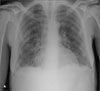

The patient had a high fever, tachycardia, tachypnea, and inspiratory rales in both lung fields but no evidence of hypoxia. White blood cell count was 23,500/μL, with 84% neutrophils. CD4+ cell count was 679/μL (well within the normal range). A chest radiograph revealed bibasilar patchy infiltrate (A).